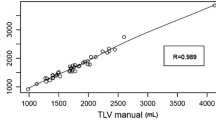

Major hepatectomy causes a risk of postoperative liver dysfunction, failure, and infections like surgical site infection. Preoperative assessment of the liver volume and function of the remnant liver is a mandatory prerequisite before performing such surgery. The aim of this work is to develop and test a software application for evaluation of the residual function of the liver prior to the intervention of the surgeons. For this purpose, a technique for evaluation of liver volume from computed tomography (CT) images has been developed. Furthermore, the methodology algorithms were implemented and incorporated within a software tool with three basic functionalities: volume determination based on segmentation of liver from CT images, virtual tumour resection and estimation of the residual liver function and 3D visualisation. Forty-one sets of abdominal CT images consisting of different number of tomographic slice images were used to test and evaluate the proposed approach. Volumes that were obtained after manual tracing by two surgeon experts showed a relative difference of 3.5 %. The suggested methodology was encapsulated within an application with user-friendly interface that allows surgeons interactively to perform virtual tumour resection, to evaluate the relative residual liver and render the final result. Thereby, it is a tool in the surgeons’ hands that significantly facilitates their duties, saves time, and allows them to objectively evaluate the situation and take the right decisions. At the same time, the tool appears to be appropriate educational instrument for virtual training of young surgeon specialists.